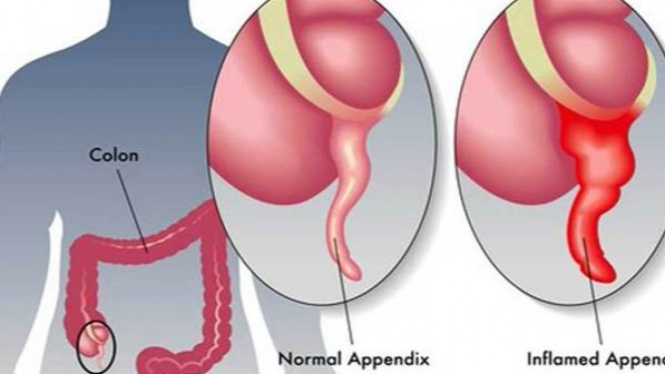

Cari Tahu Letak Dan Penyebab Usus Buntu

Cari Tahu Letak Dan Penyebab Usus Buntu